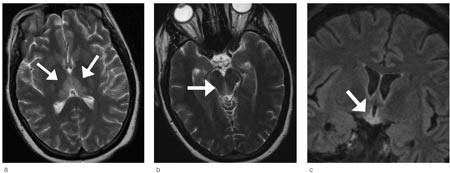

MR-kontroll fire uker etter den første undersøkelsen viste tilbakegang av forandringene i hjernestammen og fortsatt bilateral lesjon i thalamus (fig 2).

Ved utskrivningen hadde pasienten ingen nystagmus, men lett ataksi, og hukommelsen hadde bedret seg. Ifølge pårørende og henne selv var hun som før sykdommen. Nevropsykologisk testing seks uker etter utskrivning viste bedring av psykomotoriske funksjoner, intakt psykomotorisk tempo og en liten bedring i hukommelsen, som fortsatt var nedsatt. MR viste fullstendig normalisering av signalforandringene i thalamus. Ved kontroll etter fire måneder var pasientens tilstand uforandret med lett ataksi, det var ingen nystagmus eller åpenbar svikt i hukommelsen.

Vi baserte diagnosen på den nevnte triaden konfusjon, øyemuskelpareser og ataksi samt karakteristiske MR-funn (10). Denne pasienten hadde symmetriske områder med forhøyet T2-signal i dorsomediale thalamus, periakveduktalt i mesencefalon, i hypothalamus og i corpora mammillaria, noe som er typisk for Wernickes encefalopati (10) – (12). Hos enkelte pasienter vil man se kontrastopptak i disse lesjonene, men dette er ikke obligat. Hos vår pasient ble det ikke gitt intravenøs kontrast. Diffusjonsvektede MR-bilder er en sensitiv metode for å påvise intracellulært ødem hvor diffusjonen er redusert. Ved hjerneinfarkter betyr redusert diffusjon som regel en irreversibel vevsskade, som utvikles til nekrose. Det er de siste årene kommet flere rapporter som viser at enkelte av pasientene med Wernickes encefalopati har redusert diffusjon i mediale thalamus (11, 12). I utgangspunktet vil et slikt MR-funn indikere en alvorligere prognose med større risiko for vevshenfall. Hos vår pasient ble det ikke påvist redusert diffusjon. Det er også typisk å se en tydelig tilbakegang av signalforandringene ved MR-undersøkelse etter få dagers behandling med tiamin (10). Hos vår pasient observerte vi dette. Ved den første kontrollundersøkelsen var det en begynnende normalisering, og etter 2 1/2 måneder var normaliseringen fullstendig.